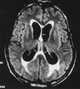

Metastatic adenocarcinoma

Adenocarcinoma (; plural adenocarcinomas or adenocarcinomata ) (AC) is a type of cancerous tumor that can occur in several parts of the body. It is defined as neoplasia of epithelial tissue that has glandular origin, glandular characteristics, or both. [Source: Wikipedia ]